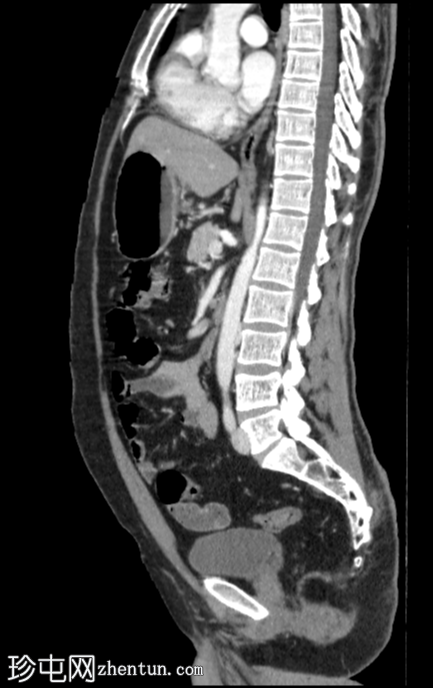

矢状位增强扫描(门静脉期)

CT扫描显示右肾上半部可见一部分边界清晰的肿块,其密度成分包含软组织和脂肪。

其余腹腔脏器未见明显异常。

可见累及L4椎体的血管瘤。

目前的CT

影像

学表现为右侧肾血管平滑肌脂肪瘤,无内部出血。